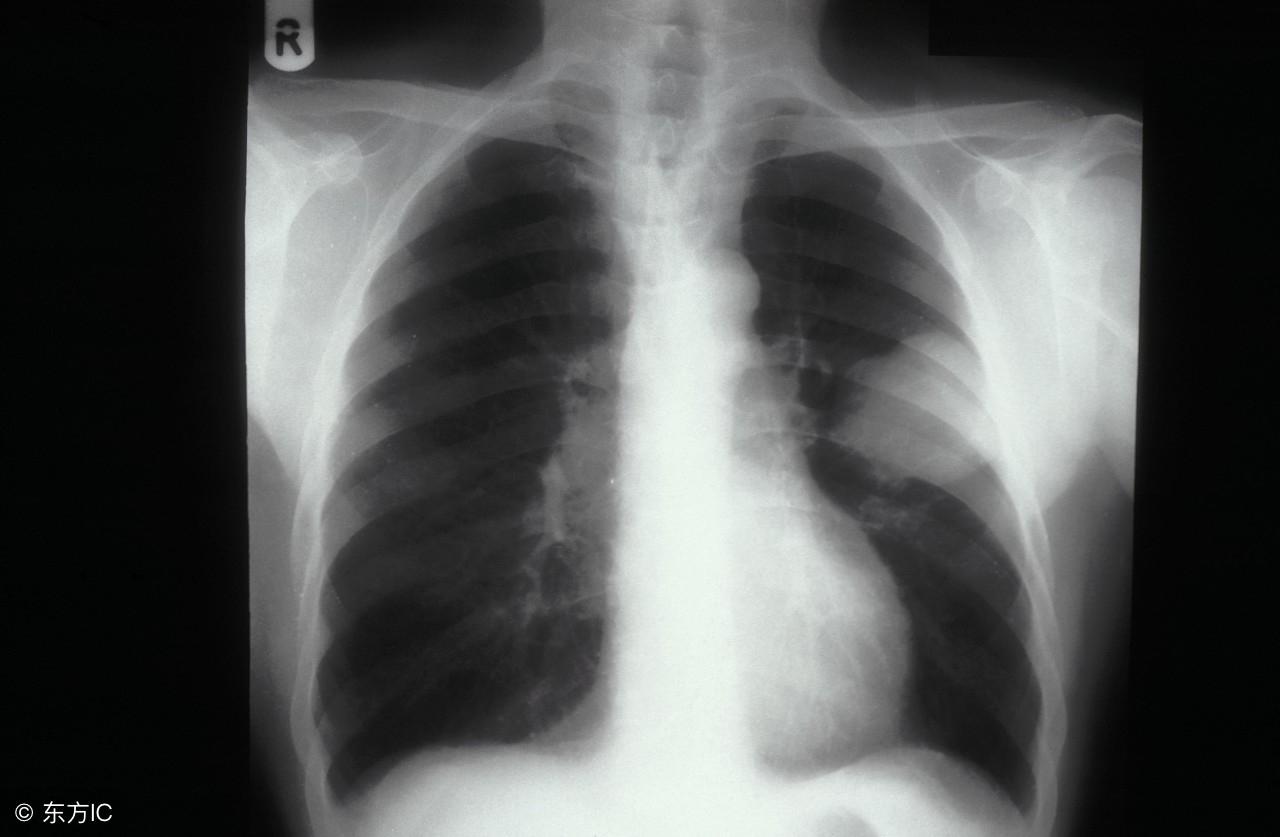

吸烟在生活中似乎成为一种常态,但是临床发现很多肺癌患者都有多年的吸烟史。肺癌给人们带来的危害极大,若是治疗不及时或是选择不适宜的治疗方法,都有可能会形成并发症,那肺癌常见并发症是什么?通过下面的介绍我们来了解一下。